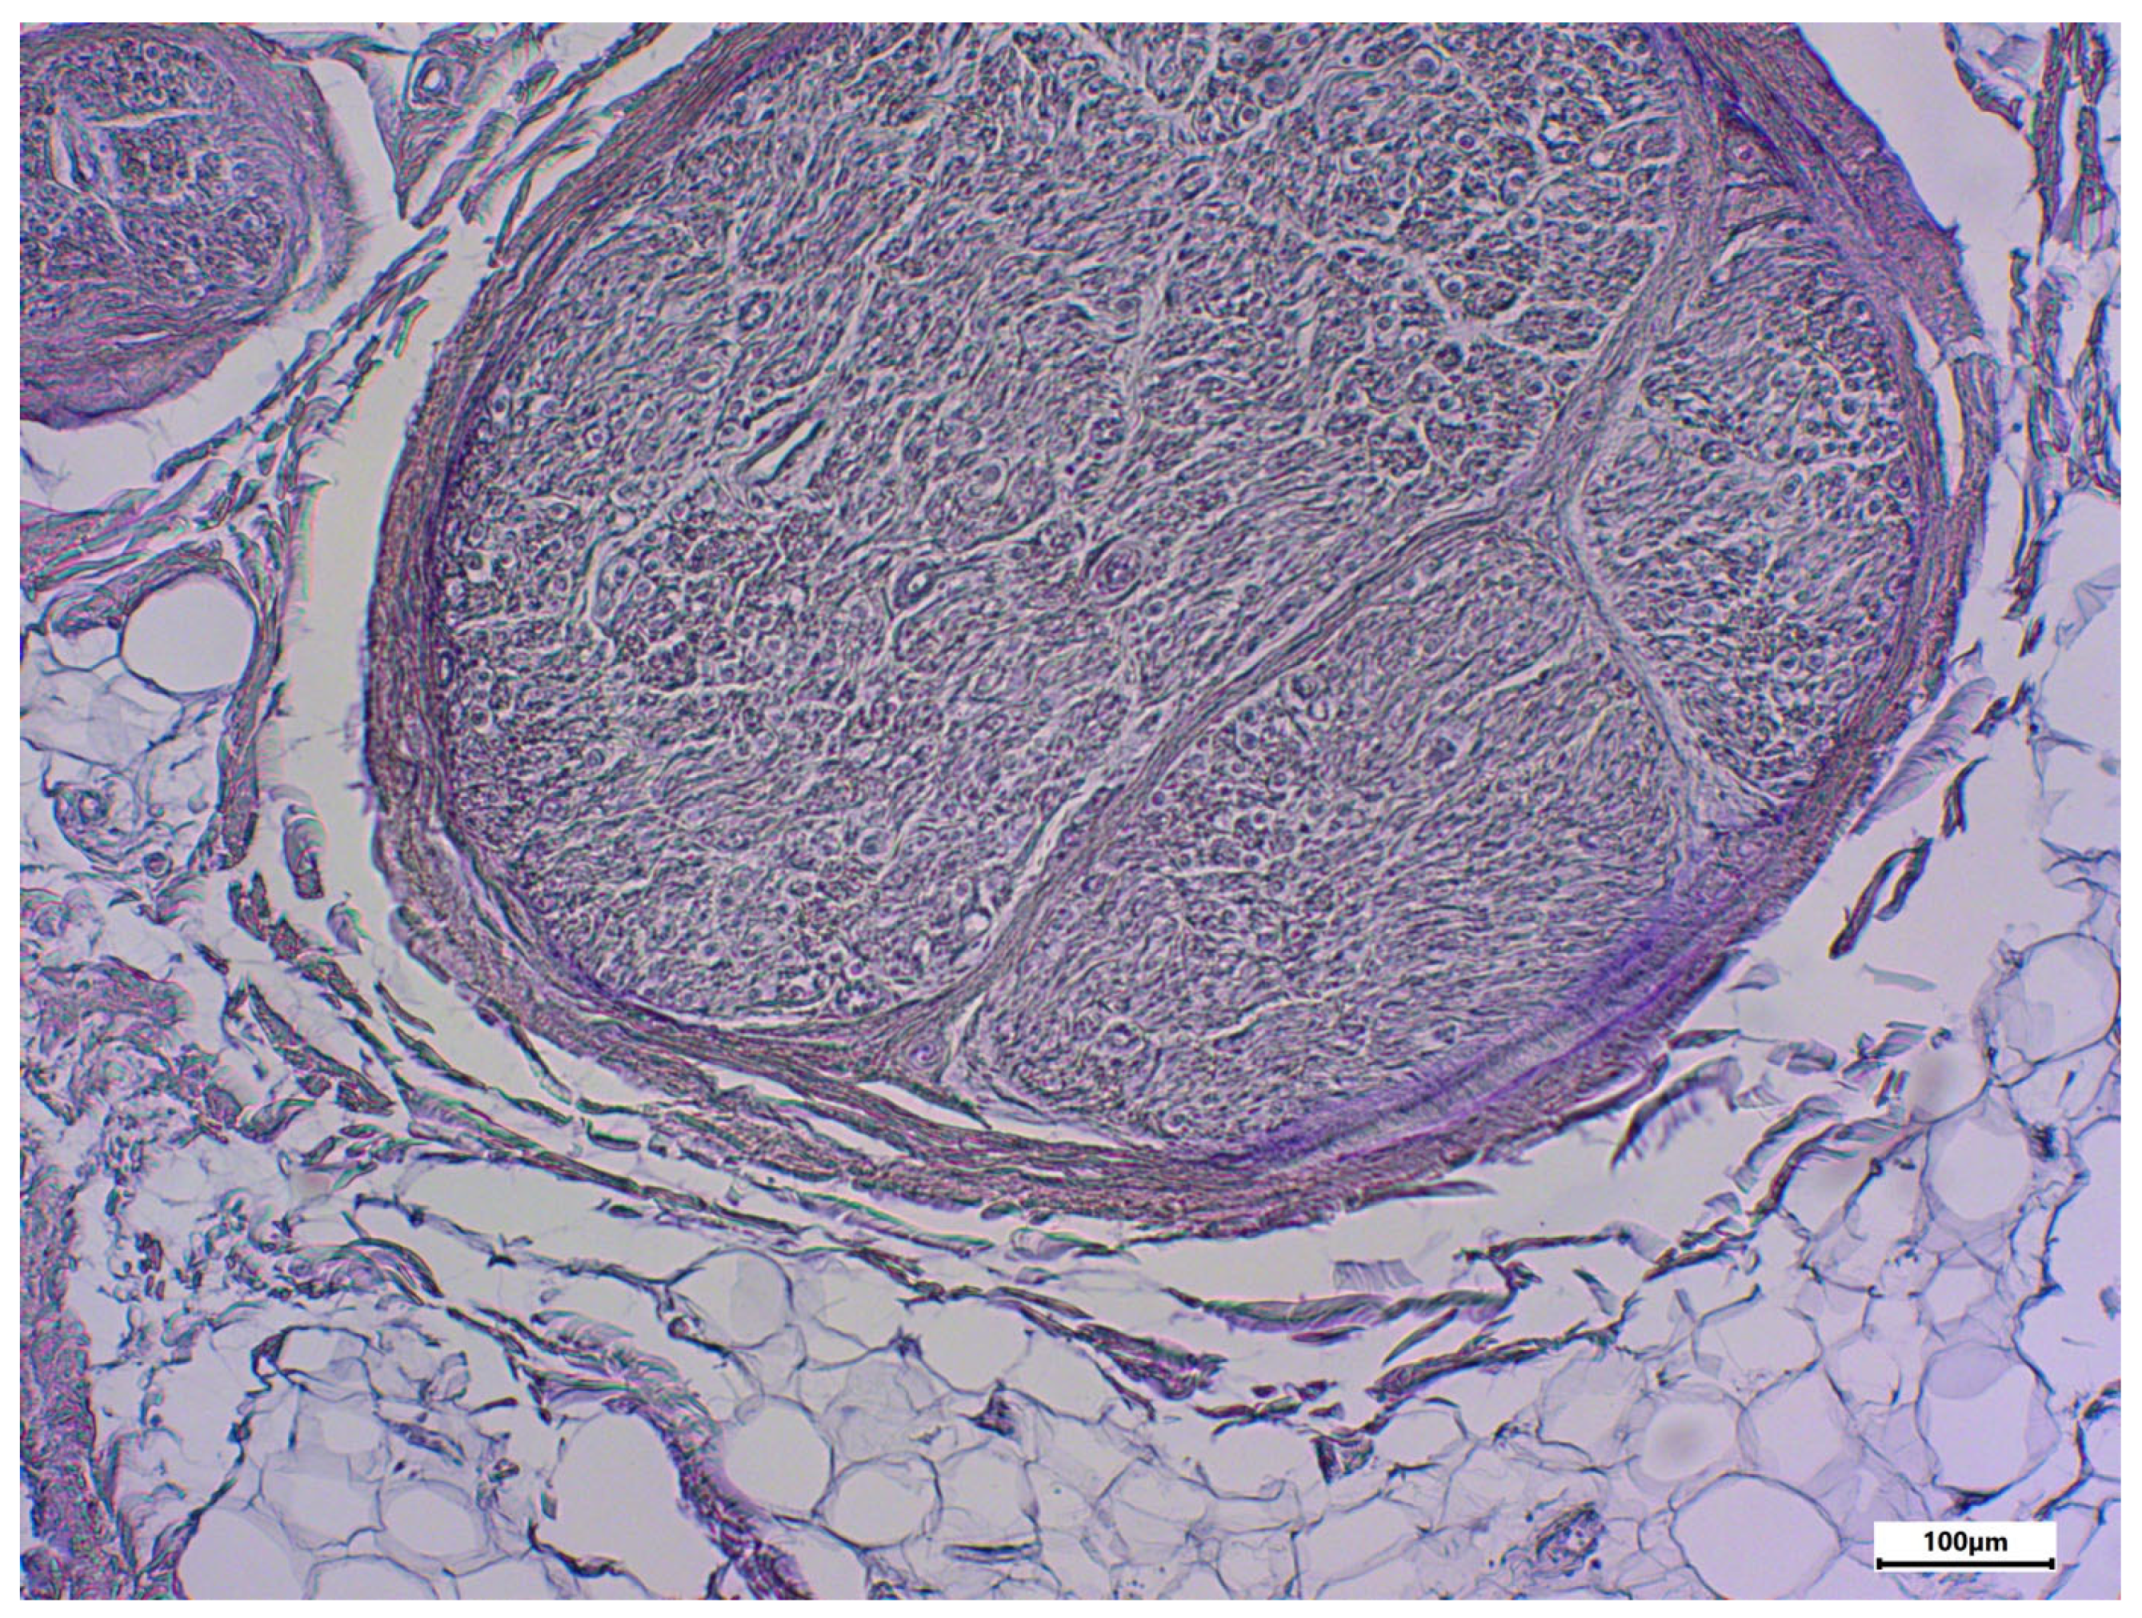

3. Results